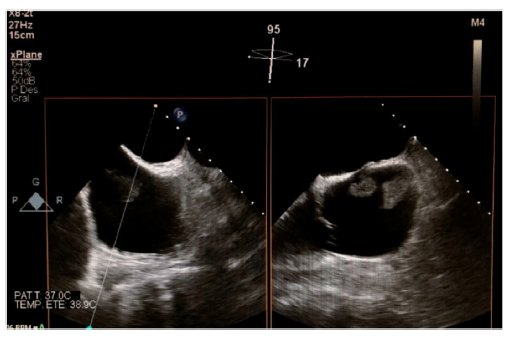

Varón de 70 años de edad, quien acudió a urgencias por episodio vasovagal con hallazgo incidental de fibrilación auricular con respuesta ventricular controlada, que se trató de manera ambulatoria mediante anticoagulación oral con acenocumarol. Durante el control ambulatorio, dos meses después, se hizo ecocardiograma transtorácico en el que se evidenció masa auricular derecha de gran tamaño (fig. 1), motivo por el cual fue ingresado. Se completó el estudio con un ecocardiograma transesofágico que reportó dos masas contiguas (32x18mm y 16x22mm) en la desembocadura de la vena cava inferior, dependientes de la válvula de Eustaquio, que atravesaban la aurícula derecha y alcanzaban el septo interauricular sin comprometer la función de la válvula tricúspide (figs. 2 y fig 3). Como primera posibilidad diagnóstica se planteó un mixoma auricular y ante la posibilidad de embolización se optó por manejo quirúrgico, no sin antes efectuar una coronariografía, que no reportó lesiones; se programó para resección del mixoma. Durante la cirugía se hallaron dos masas de aspecto fibroelástico (fig. 4 ) que no se relacionaban con el septo y que al ser resecadas no alteraban la competencia de la válvula tricúspide. La cirugía y el postoperatorio cursaron sin complicaciones y el estudio anatomo-patológico informó que las masas correspondían a trombos, sin hallazgos de componente tumoral. Durante el seguimiento a seis meses permanecía asintomático y en ritmo de fibrilación auricular.

Figura 3 Se observan las dos masas alcanzando el septo interauricular sin comprometer la función de la válvula tricúspide en el ecocardiograma transesofágico.